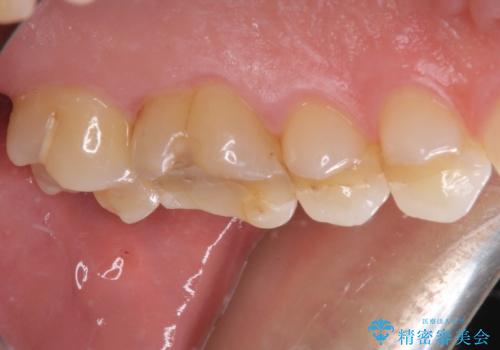

ゴールドインレーは銀歯のインレーやセラミックインレーと比べ、「技工操作の精度が高く、適合が著しく良い」というメリットがあります。特に上の奥歯は歯科医師の操作が行いにくいため、「適合の良さ」は再治療のリスクを防ぐ上でとても重要な要素となります。

上の奥歯は金属色が見えることもないため、審美的な問題は全くありません。

咬み心地はとても良好で、全く違和感がなく、患者様には大変満足していただきました。